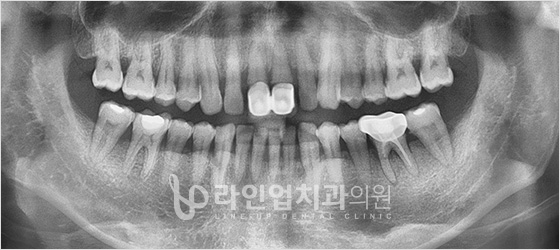

치료전

Before

치료후

After

윗 어금니 임플란트 (56세/남/ 2014.05.02~2014.10.06)